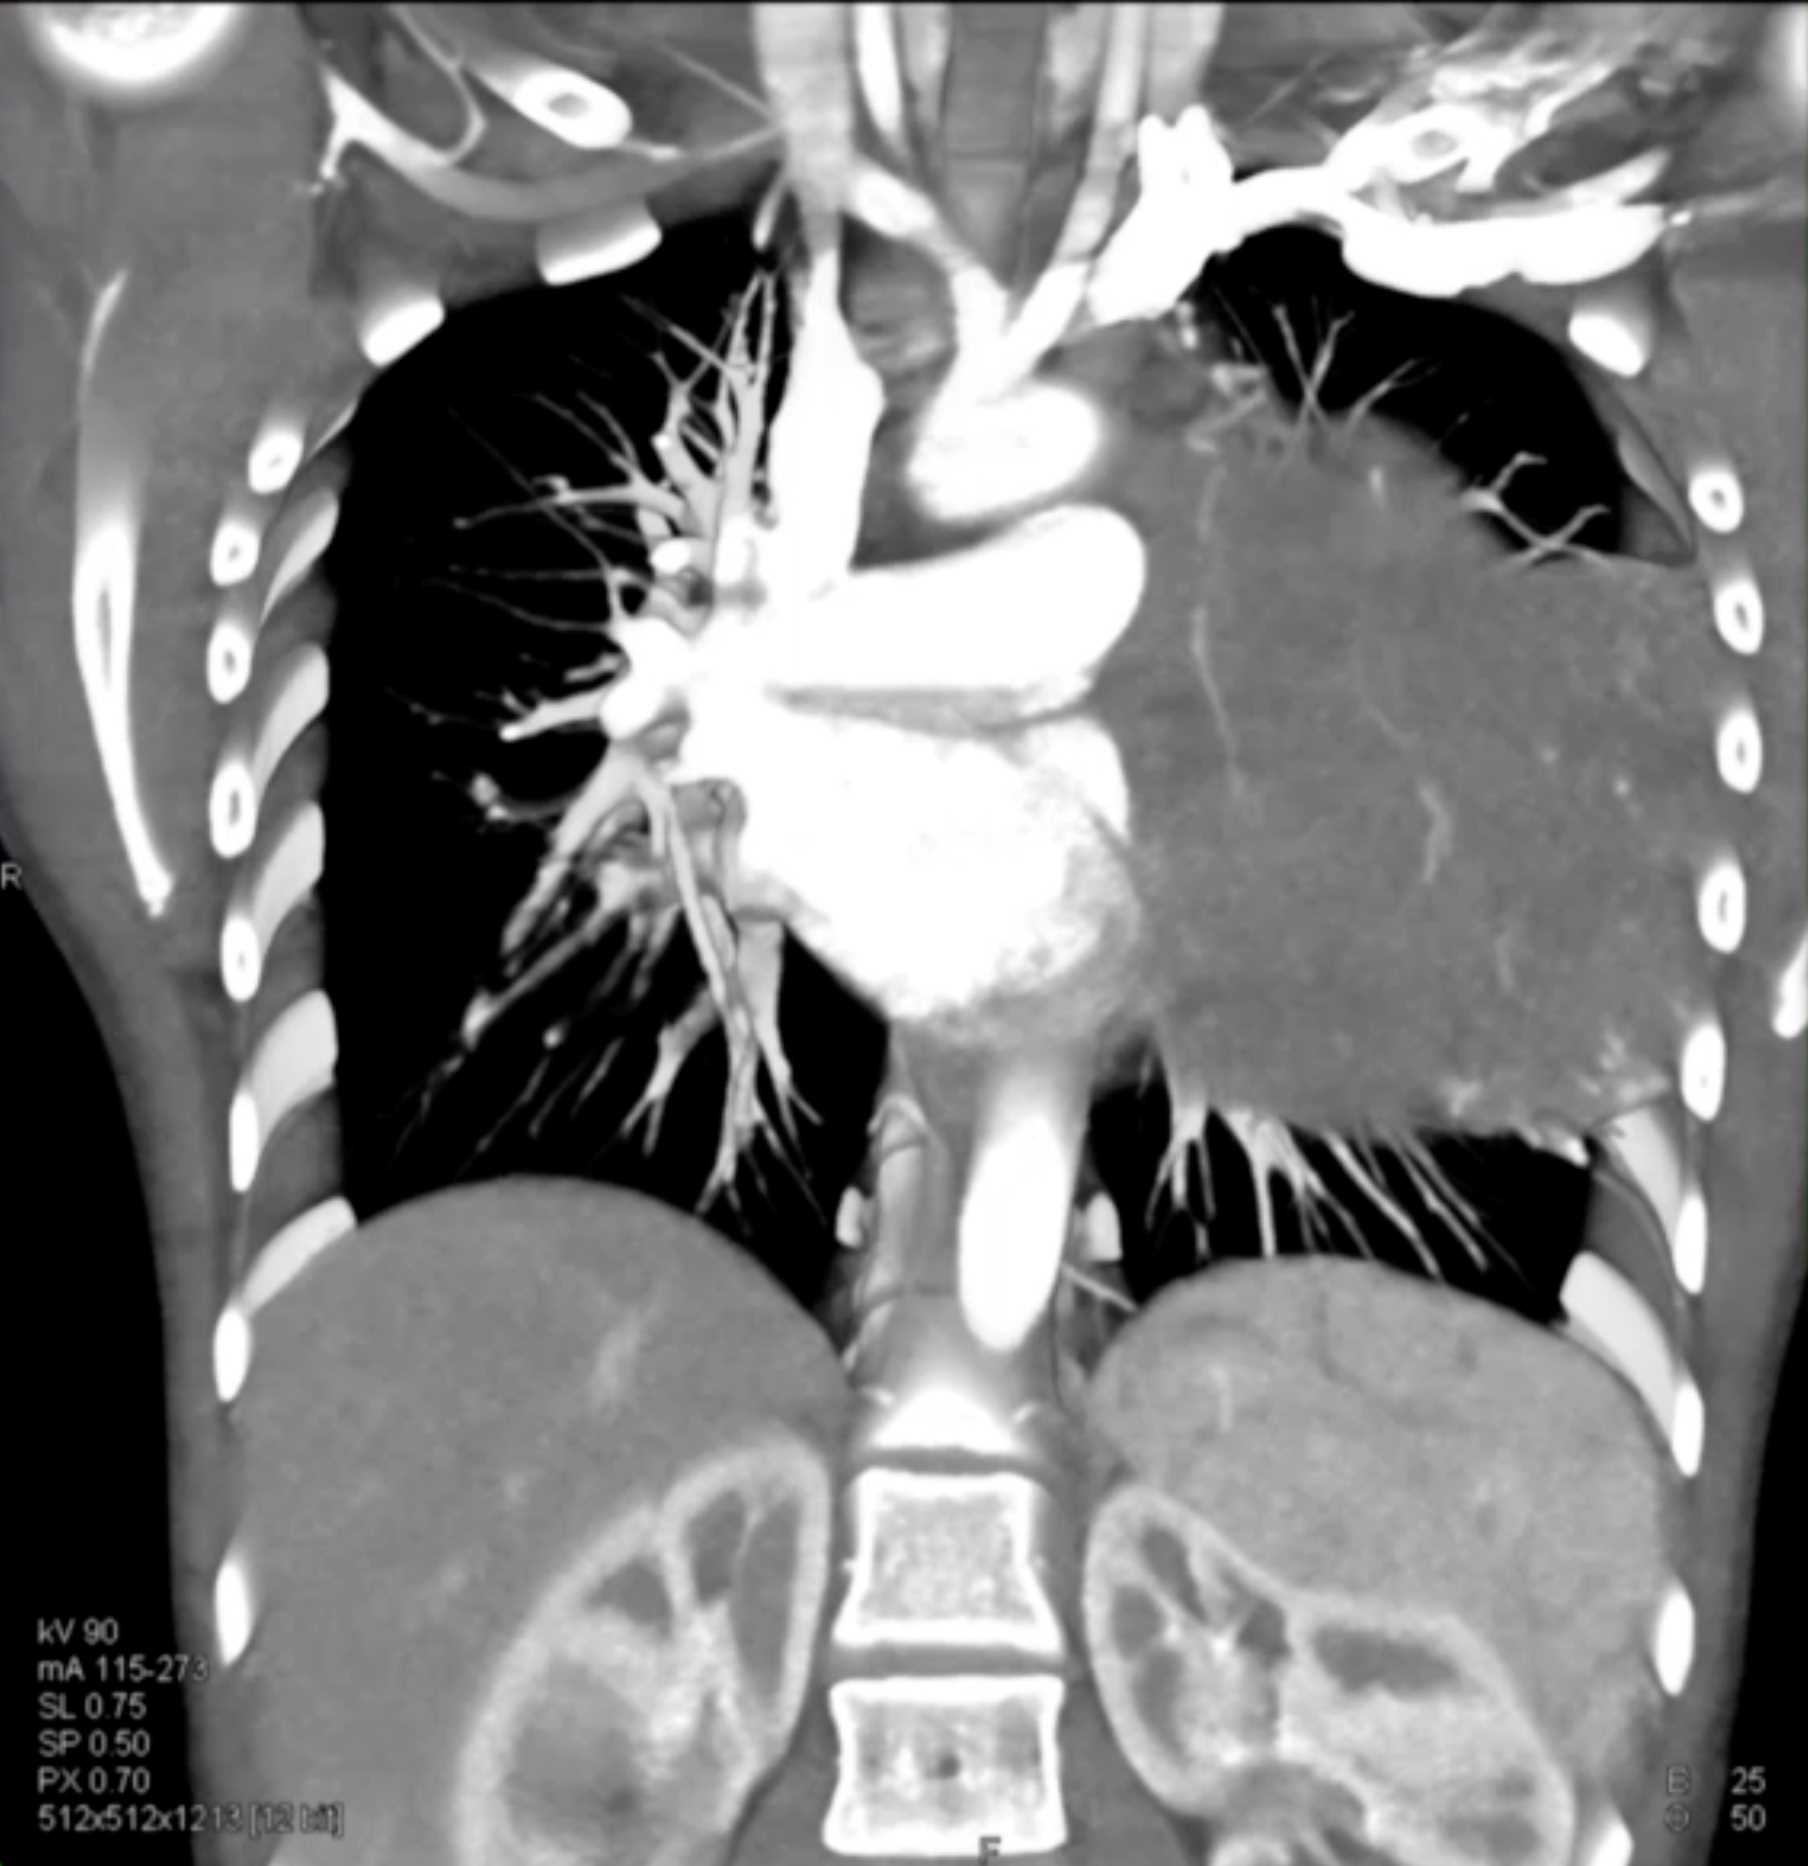

Subtle Adenocarcinoma Pancreas